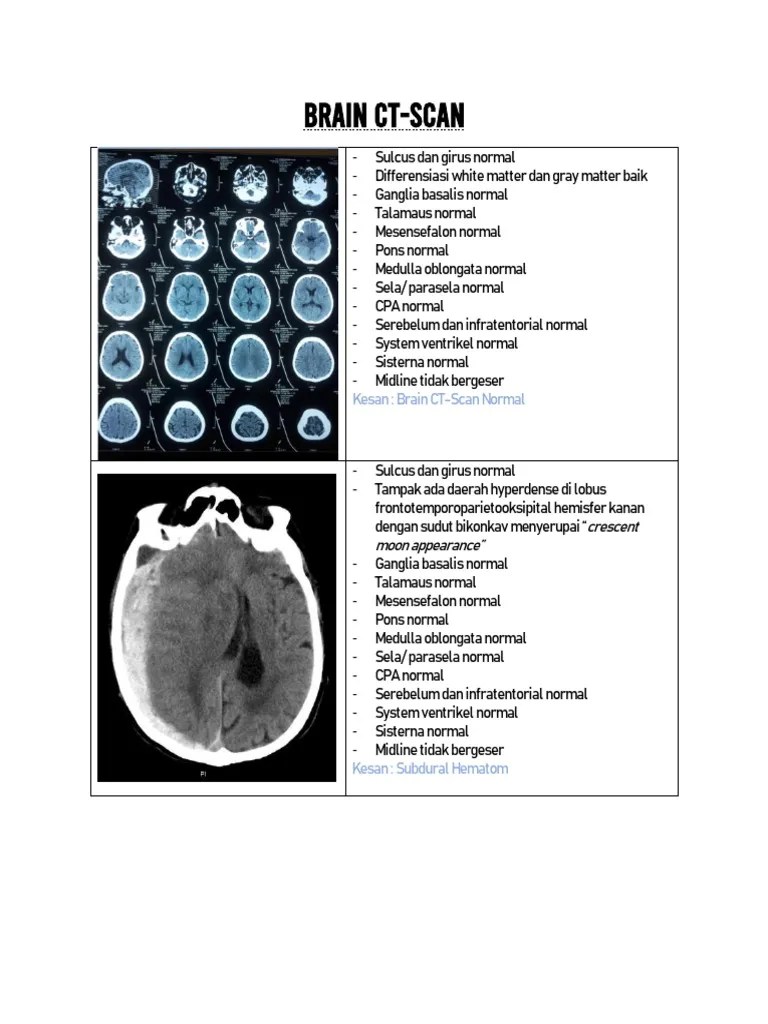

brain ct scan  ct scan cerebrospinal fluid 768×1024

brain ct scan ct scan cerebrospinal fluid